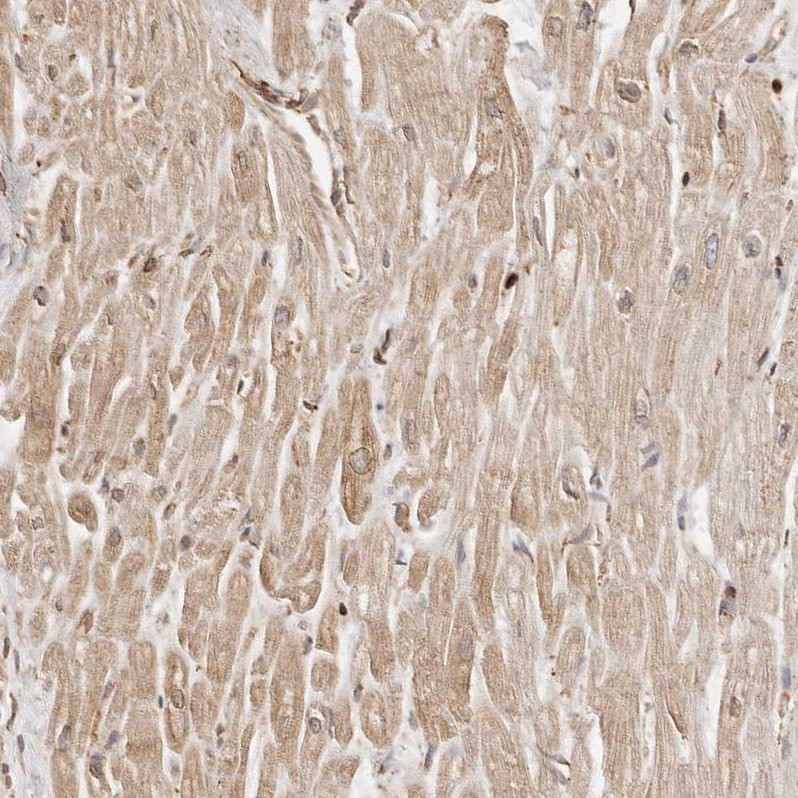

Staining of human heart muscle shows weak cytoplasmic positivity in cardiomyocytes.